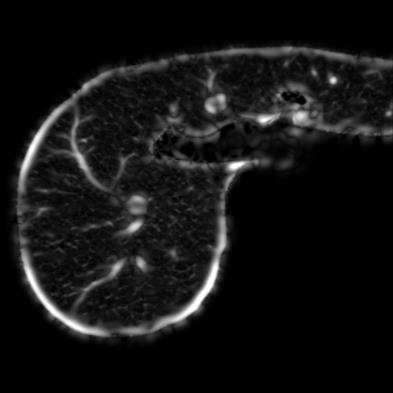

Manually segmenting the hepatic vessels from Computer Tomography (CT) is far more expertise-demanding and laborious than other structures due to the low-contrast and complex morphology of vessels, resulting in the extreme lack of high-quality labeled data. Without sufficient high-quality annotations, the usual data-driven learning-based approaches struggle with deficient training. On the other hand, directly introducing additional data with low-quality annotations may confuse the network, leading to undesirable performance degradation. To address this issue, we propose a novel mean-teacher-assisted confident learning framework to robustly exploit the noisy labeled data for the challenging hepatic vessel segmentation task. Specifically, with the adapted confident learning assisted by a third party, i.e., the weight-averaged teacher model, the noisy labels in the additional low-quality dataset can be transformed from "encumbrance" to "treasure" via progressive pixel-wise soft-correction, thus providing productive guidance. Extensive experiments using two public datasets demonstrate the superiority of the proposed framework as well as the effectiveness of each component.

翻译:将来自计算机地形学(CT)的肝脏船只人工分割,由于船只的低调和复杂形态,由于低调和复杂的形态,造成极端缺乏高质量的标签数据,因此比其他结构更需要专门知识和难度大得多。如果没有足够的高质量的说明,通常的数据驱动的基于学习的方法就会与不足的培训斗争。另一方面,直接引进低质量说明的额外数据可能会混淆网络,导致不良的性能退化。为了解决这一问题,我们提议建立一个新的、由教师协助的、有说服力的、有说服力的学习框架,为具有挑战性的肝脏船只分解任务强有力地利用响亮的标签数据。具体地说,在第三方(即加权平均教师模式)的协助下,经过变通的自信学习后,额外低质量数据集中的噪音标签可以从“阻力”转变为“压力”,通过渐进式的像素方法的软校正,从而提供富有成效的指导。使用两个公共数据集进行的广泛实验,显示了拟议框架的优越性以及每个组成部分的效能。